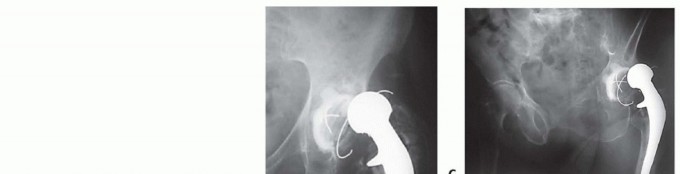

DEFINITION Hip reimplantation refers to the insertion of another prosthesis after removal of the original, in…